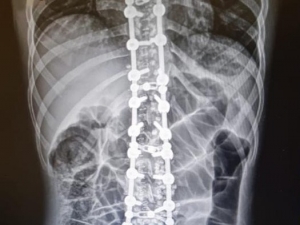

Sırt Ağrısı Kemik Erimesini İşaret Ediyor Olabilir